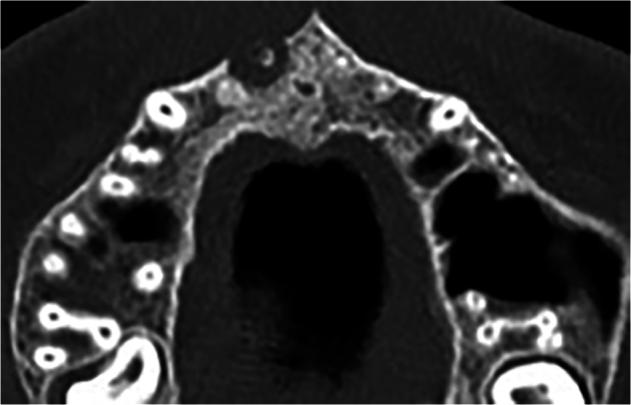

A randomized controlled trial was conducted on 41 patients who had 60 permanent teeth in the maxillary incisors that were accompanied by large-sized periapical lesions. The included teeth were radiographed with cone beam computed tomography (CBCT) images and divided equally into two groups according to the endodontic treatment statute (30 untreated previous cases and 30 retreated cases). Subsequently, teeth received uniform preparation, irrigation, and dressing procedures. Then each group was divided equally according to the used sealer (15 teeth obturated using AH plus sealer with LCT and 15 teeth obturated using BC sealer with SCT). All cases were followed up after 6 and 12 months with CBCT images. Subsequently, the change in periapical lesion diameter (PLD) was observed as an indicator to determine the treatment outcome score. One-way ANOVA and Mann-Whitney U test were used to analyze the PLD changing and scoring the treatment outcome during the follow-up periods. The significance level was set at α = 0.05.

对41例上颌切牙有60颗恒牙且伴有大型根尖周病变的患者进行了一项随机对照试验。纳入的牙齿用锥形束计算机断层扫描(CBCT)成像进行放射照相,并根据牙髓治疗情况平均分为两组(30例既往未治疗病例和30例再治疗病例)。随后,对牙齿进行统一的预备、冲洗和换药程序。然后根据所用封闭剂将每组再平均分为两组(15颗牙齿使用AH plus封闭剂和LCT进行根管充填,15颗牙齿使用BC封闭剂和SCT进行根管充填)。所有病例在6个月和12个月后用CBCT图像进行随访。随后,观察根尖周病变直径(PLD)的变化作为确定治疗结果评分的指标。采用单因素方差分析和曼-惠特尼U检验分析随访期间PLD的变化及治疗结果评分。显著性水平设定为α = 0.05。